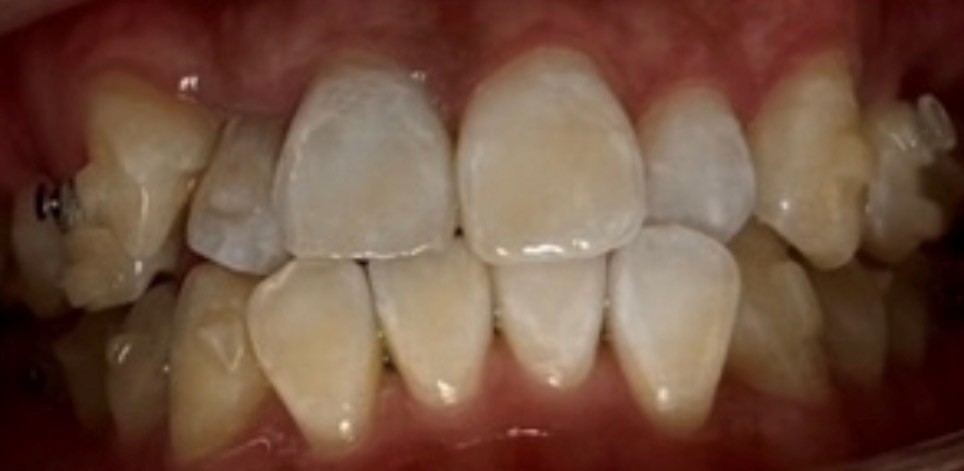

症例画像

治療期間 1回(7分×10分×10分)

治療費用 9800

主訴 歯の着色

治療内容 オフィスホワイトニング

副作用リスク→知覚過敏のようなしみ、痛み。アタッチメントの下の色むら